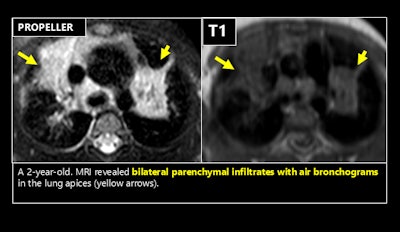

“MRI demonstrates high sensitivity for detecting pneumonia, its complications (e.g., necrosis, abscess), and other lung abnormalities,” noted Dr. Emre Ruhat Avci and his colleagues from the Department of Radiology at Dokuz Eylül University Faculty of Medicine, Izmir, Turkey. “It also aids in narrowing differential diagnoses by identifying specific features such as necrosis and cavitation in tuberculosis or the characteristic hydatid cysts in Echinococcus infections.”

Techniques such as undersampling k-space or employing specialized k-space sampling strategies, including periodically rotated overlapping parallel lines with enhanced reconstruction (PROPELLER or BLADE), are effective in minimizing respiratory motion artifacts and improving image quality in challenging cases. Figures courtesy of Dr. Emre Ruhat Avci et al and presented at ECR 2025.